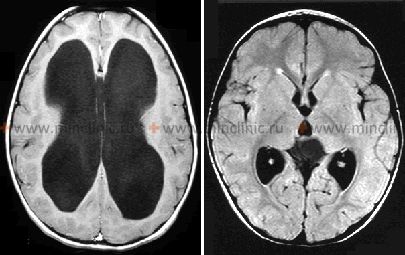

შემაერთებელი (ღია) ჰიდროცეფალია ტვინშიდა სისხლჩაქცევის შემდეგ ანევრიზმის გასკდომის დროს

შემაერთებელი (ღია) ჰიდროცეფალია არის ხშირი და მნიშვნელოვანი გართულება, რომელიც შეიძლება განვითარდეს ანევრიზმული სუბარაქნოიდული სისხლჩაქცევის (სას) შემდეგ [1, 2]. ობსტრუქციული (დახურული) ჰიდროცეფალიისგან განსხვავებით, სადაც პარკუჭოვან სისტემაში ფიზიკური ბლოკადაა, შემაერთებელი ჰიდროცეფალიის დროს დარღვეულია თავ-ზურგტვინის სითხის (თზს, ლიქვორის) უკუშეწოვა (აბსორბცია) სისხლძარღვოვან კალაპოტში, მიუხედავად იმისა, რომ თზს-ს თავისუფლად შეუძლია მოძრაობა პარკუჭებსა და სუბარაქნოიდულ სივრცეს შორის [1, 2]. ეს იწვევს თზს-ის დაგროვებას, პარკუჭების გაფართოებას და ინტრაკრანიალური (ქალაშიდა) წნევის (იწ) მომატებას [1].

მთავარი მიზეზი თზს-ის აბსორბციის დარღვევაა [1, 2]. სას-ის დროს გამოყოფილი სისხლის კომპონენტები ცირკულირებს თზს-ში და შეიძლება გამოიწვიოს ანთება, ნაწიბურების წარმოქმნა ან არაქნოიდული გრანულაციების (პახიონის გრანულაციების) ფიზიკური ბლოკირება — ეს არის სპეციალიზებული სტრუქტურები, რომლებიც ძირითადად ზედა საგიტალური სინუსის გასწვრივ მდებარეობს და პასუხისმგებელია თზს-ის სისხლში უკუშეწოვაზე [1]. როდესაც აბსორბცია მცირდება, მაგრამ თზს-ის გამომუშავება ნორმალური ტემპით გრძელდება, თზს გროვდება, რაც იწვევს ინტრაკრანიალური (ქალაშიდა) წნევის (იწ) მომატებას და თავის ტვინის პარკუჭების (გვერდითი, მესამე და მეოთხე) გაფართოებას (დილატაციას) [1].

- ვენტრიკულომეგალია: გვერდითი, მესამე და მეოთხე პარკუჭების გაფართოება, რაც ხშირად არაპროპორციულია ნებისმიერი თანმხლები ცერებრული ატროფიის მიმართ.

- ნიშნები, რომლებიც მიუთითებს თზს-ის დინების/აბსორბციის დარღვევაზე: პერივენტრიკულური გამჭვირვალობა/შეშუპება (ტრანსეპენდიმური თზს-ის გაჟონვა), თავის ტვინის კონვექსიტალურ ზედაპირზე ქერქის ღარების გადასწორება, შუბლის რქების მომრგვალება.

- ევანსის ინდექსი (შუბლის რქის მაქსიმალური სიგანის შეფარდება თავის ქალას შიდა მაქსიმალურ დიამეტრთან) > 0.3 ხშირად გამოიყენება როგორც რაოდენობრივი მაჩვენებელი.